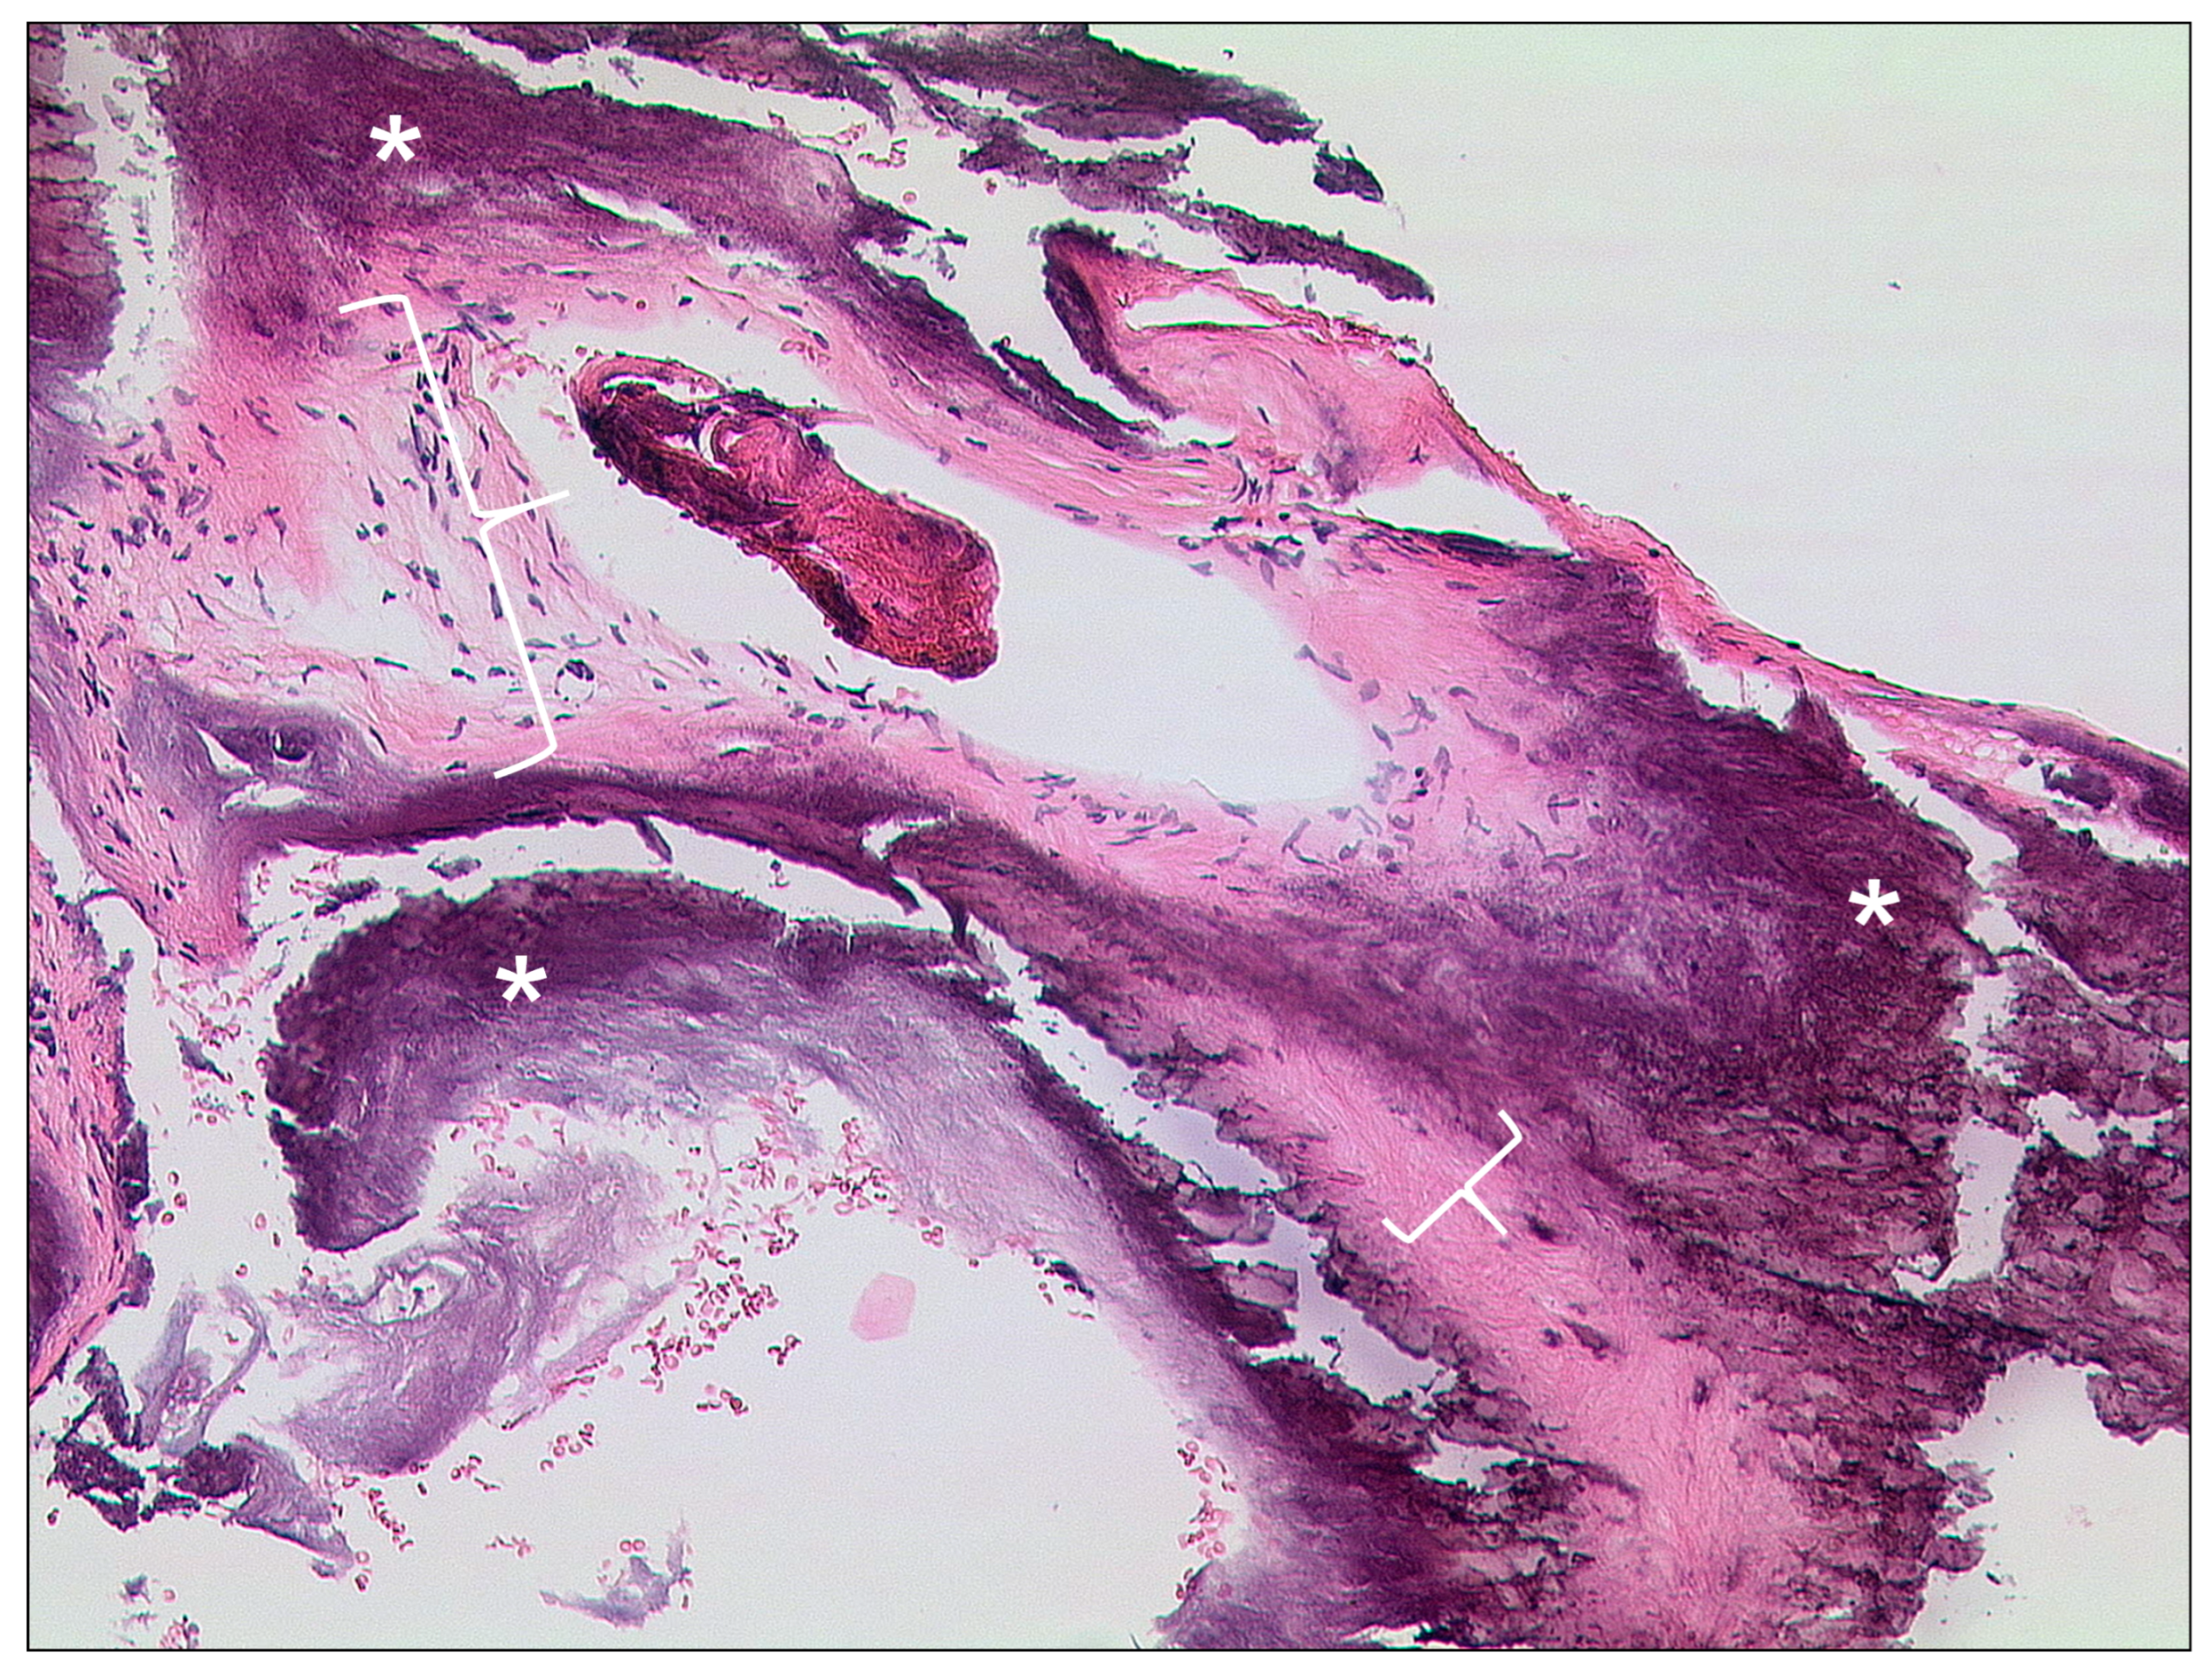

3.1.3. Auditory Canal Exostosis